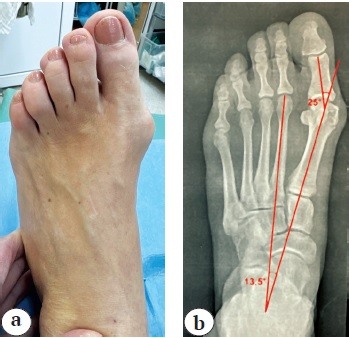

По данным рентгенограмм с нагрузкой, выполненных через 6 мес. после операции, костная мозоль полностью сформирована. Первый межплюсневый угол равен 3°, угол вальгусного отклонения первого пальца — 7° (рис. 4). Пациентка вела привычный образ жизни.

Рис. 4. Результат через 6 мес. после операции: а — внешний вид стопы; b — рентгенограмма стопы с нагрузкой в прямой проекции: костная мозоль полностью сформирована

Fig. 4. Six months after surgery:a — general view of the foot; b — stress X-ray in AP view: completed bone callus formation